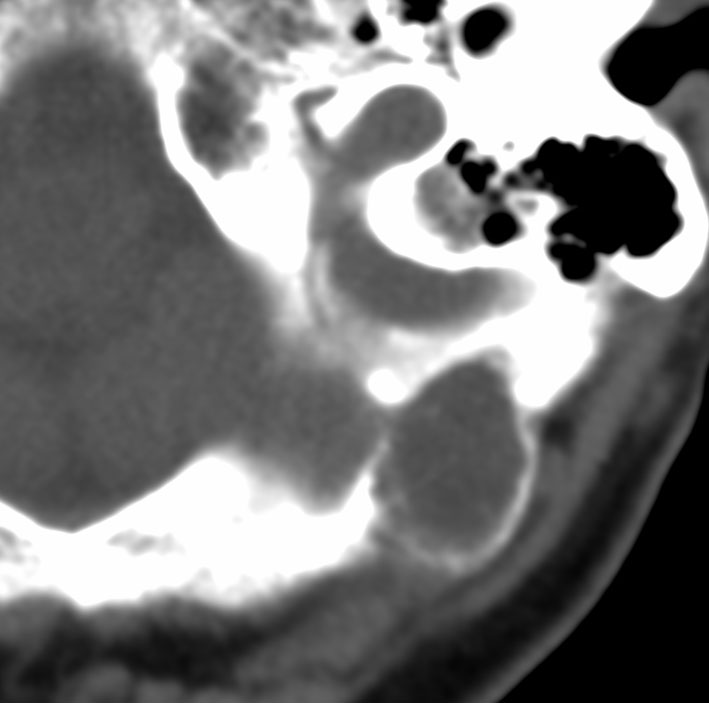

40代女性の後頭部傍矢状洞部の硬膜に発生したグレード3です。腫瘍周囲の強い浮腫のために,頭頂葉のゲルストマン症候で発症しました。術前診断は髄膜腫でしたが,腫瘍内部にのう胞(液体が溜まっている)があり,髄膜腫としては典型的な画像ではありません。右側の血管撮影にみられるように,上矢状洞が一部狭窄して腫瘍が浸潤している所見があり,腫瘍が濃染します。腫瘍の周囲の脳には出血がありました。大脳鎌と上矢状洞の壁を含めて全摘出しました。